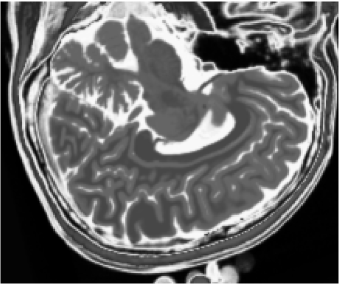

Figures 1 (band 0), 2 (band 1) and 3 (band 2) show PD- (proton density), - and -weighted MR images of the 97th slice, while figure 4 shows the R0-G1-B2 colored composition of the same slice.